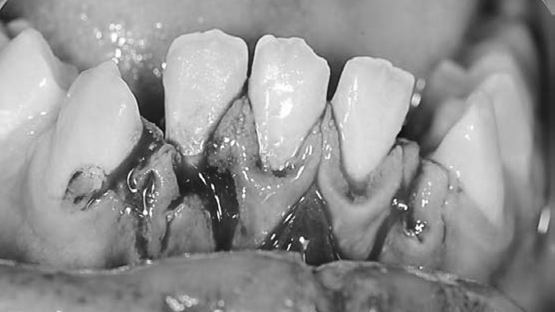

Dislokationsverletzungen im bleibenden Gebiss treten im klinischen Alltag meist plötzlich und unerwartet auf und erfordern eine rasche und strukturierte Befundung sowie eine notfallmässige Erstversorgung. Besonders bei Dislokationsverletzungen wie Avulsion, lateraler Dislokation, Extrusion und Instrusion ist die Initialversorgung ein entscheidender prognostischer Faktor für den Zahnerhalt. Am Zahntraumasymposium 2026 stehen genau diese Verletzungsmuster im Fokus. Anhand aktueller Leitlinien, Fallbeispiele und praxisnaher Empfehlungen soll vermittelt werden, wie eine strukturierte Erstbeurteilung und Notfallbehandlung im bleibenden Gebiss idealerweise erfolgt – Kompetenzen, die jede Zahnärztin und jeder Zahnarzt im klinischen Alltag sicher beherrschen sollte.